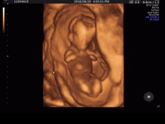

У нас будет сынок ^^ Даниэль ^^

За две недели заметно подросли 8-9 неделя ❤️ наше чудо ❤️